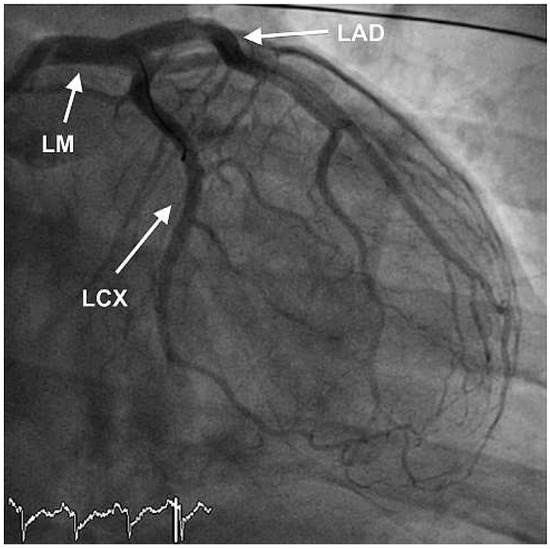

We report the case of a 47-year old man who presented with severe cardiogenic shock and signs of ST-elevation myocardial infarction. Urgent coronary angiography showed thrombotic occlusion of the mid left anterior descending artery (LAD) and the circumflex artery, as well as a [...] Read more.

We report the case of a 47-year old man who presented with severe cardiogenic shock and signs of ST-elevation myocardial infarction. Urgent coronary angiography showed thrombotic occlusion of the mid left anterior descending artery (LAD) and the circumflex artery, as well as a subtotal thrombotic occlusion of the right coronary artery without signs of relevant atherosclerotic coronary disease. The patient was treated with thrombus aspiration in all coronary vessels and PTCA of the LAD with good result. Despite thorough investigation of major nonatherosclerotic causes of myocardial infarction, which are further discussed in our case report, the case remains unsolved. Until today the patient is free of symptoms under long-term dual antiplatelet-inhibitor therapy. Full article